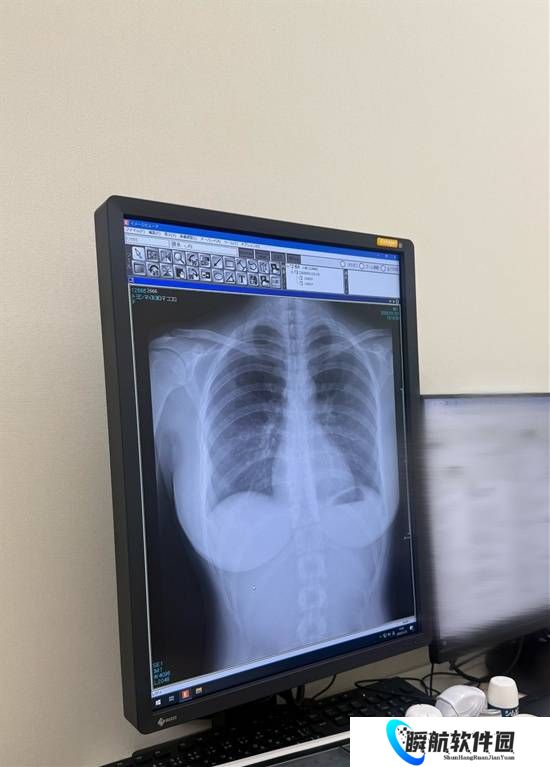

近期,她一个别出心裁的举动再次吸引了众人目光:在社交平台上公开了自己的肺部X光片。这张影像不仅展现了其健康状况,更因为日本**偶像极少公开此类个人医疗信息而引发热议。

有人则专业点评其肺部“这张胸部正位X光片显示肺部状况极佳。双肺野清晰,未见浸润、结节或胸腔积水。心脏轮廓正常,胸廓骨骼未见骨折或异常。”,